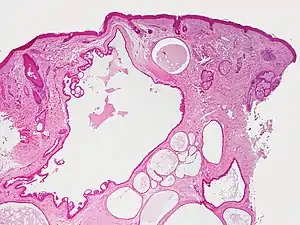

Hidrocystoma

Hidrocystoma (also known as cystadenoma,[1] a Moll's gland cyst,[1] and a sudoriferous cyst[1]) is an adenoma of the sweat glands.[2]: 787

Hidrocystomas are cysts of sweat ducts, usually on the eyelids.[3]: 664 They are not tumours (a similar-sounding lesion called hidroadenoma is a benign tumour).

Hidrocystomas usually arise from apocrine glands. They are also called cysts of Moll or sudoriferous cysts. A type of hidroadenoma that arises from eccrine glands is uncommon.